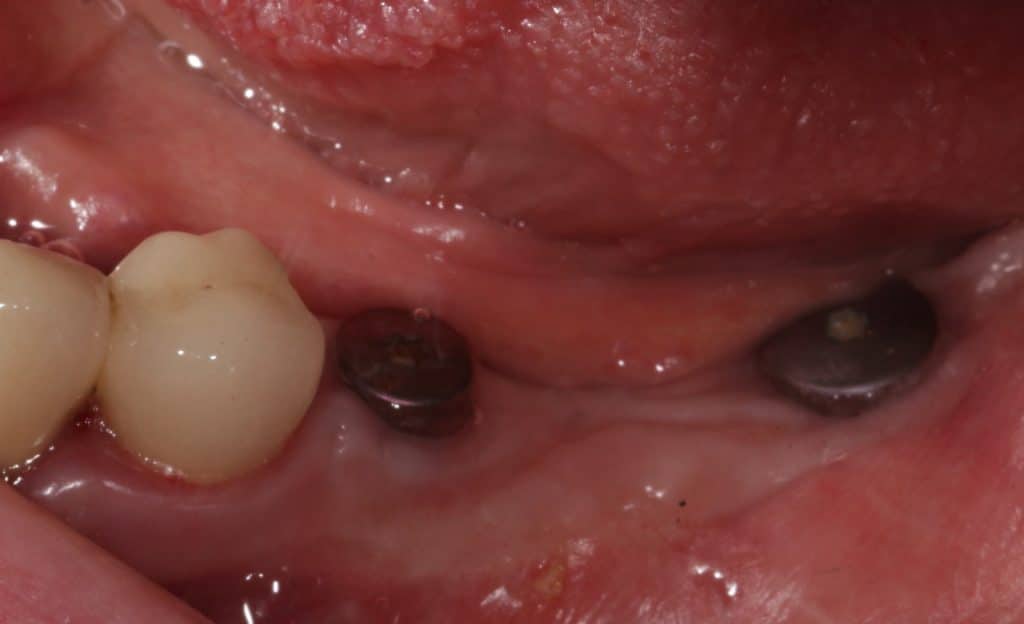

Presence of two broken implants in position 3.5 and 3.7

Initial clinical situation- Occlusal view

Initial clinical situation- Detail of the area

Tissue condition at the time of reopening